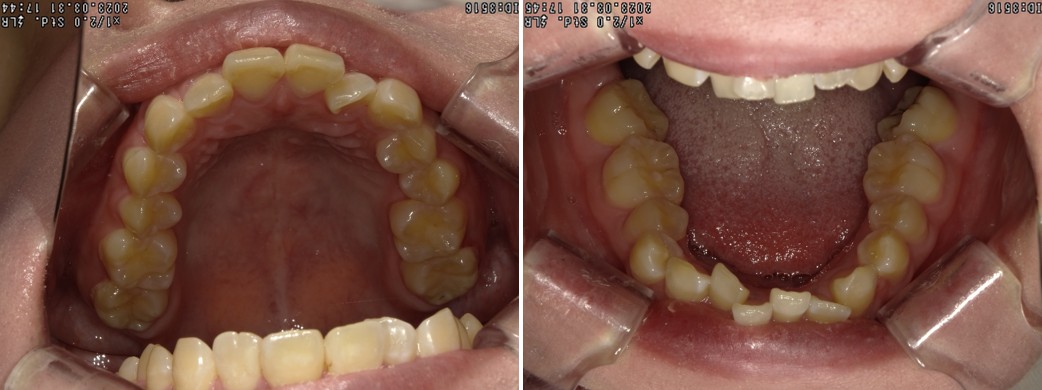

叢生を改善した1症例

治療前 ![]() |

相談内容 |

前歯がずれているのが気になる |

診断結果 |

骨格 軽度Ⅱ級 |

ご提案内容 |

全顎アライナー矯正(クリアコレクト)+ ワイヤー矯正 |

治療期間 |

12ヶ月 |

治療回数 |

12回 |

治療費 |

税込78万円(検査料・調整料込み) |

治療のリスク |

装着時間が不足すると歯が予定通りに動かず、治療が長引くことがあります。 |

クリニックより |

アライナー矯正で8ヶ月ほど、ワイヤー矯正で4ヶ月ほど治療を行なっています。 |